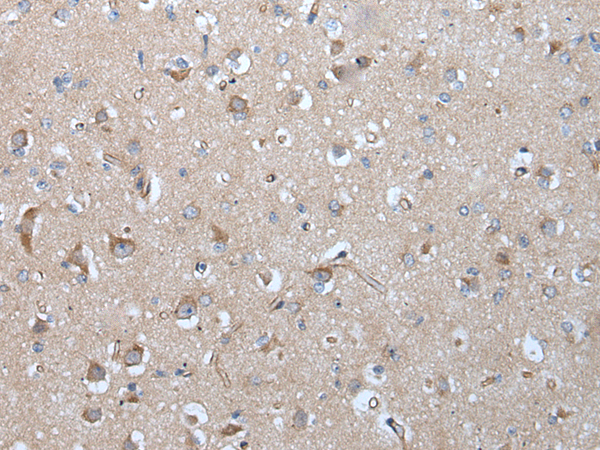

分类: 科研抗体货号: P12893别名: MCOPS11应用: IHC反应种属: Human, Mouse, Rat